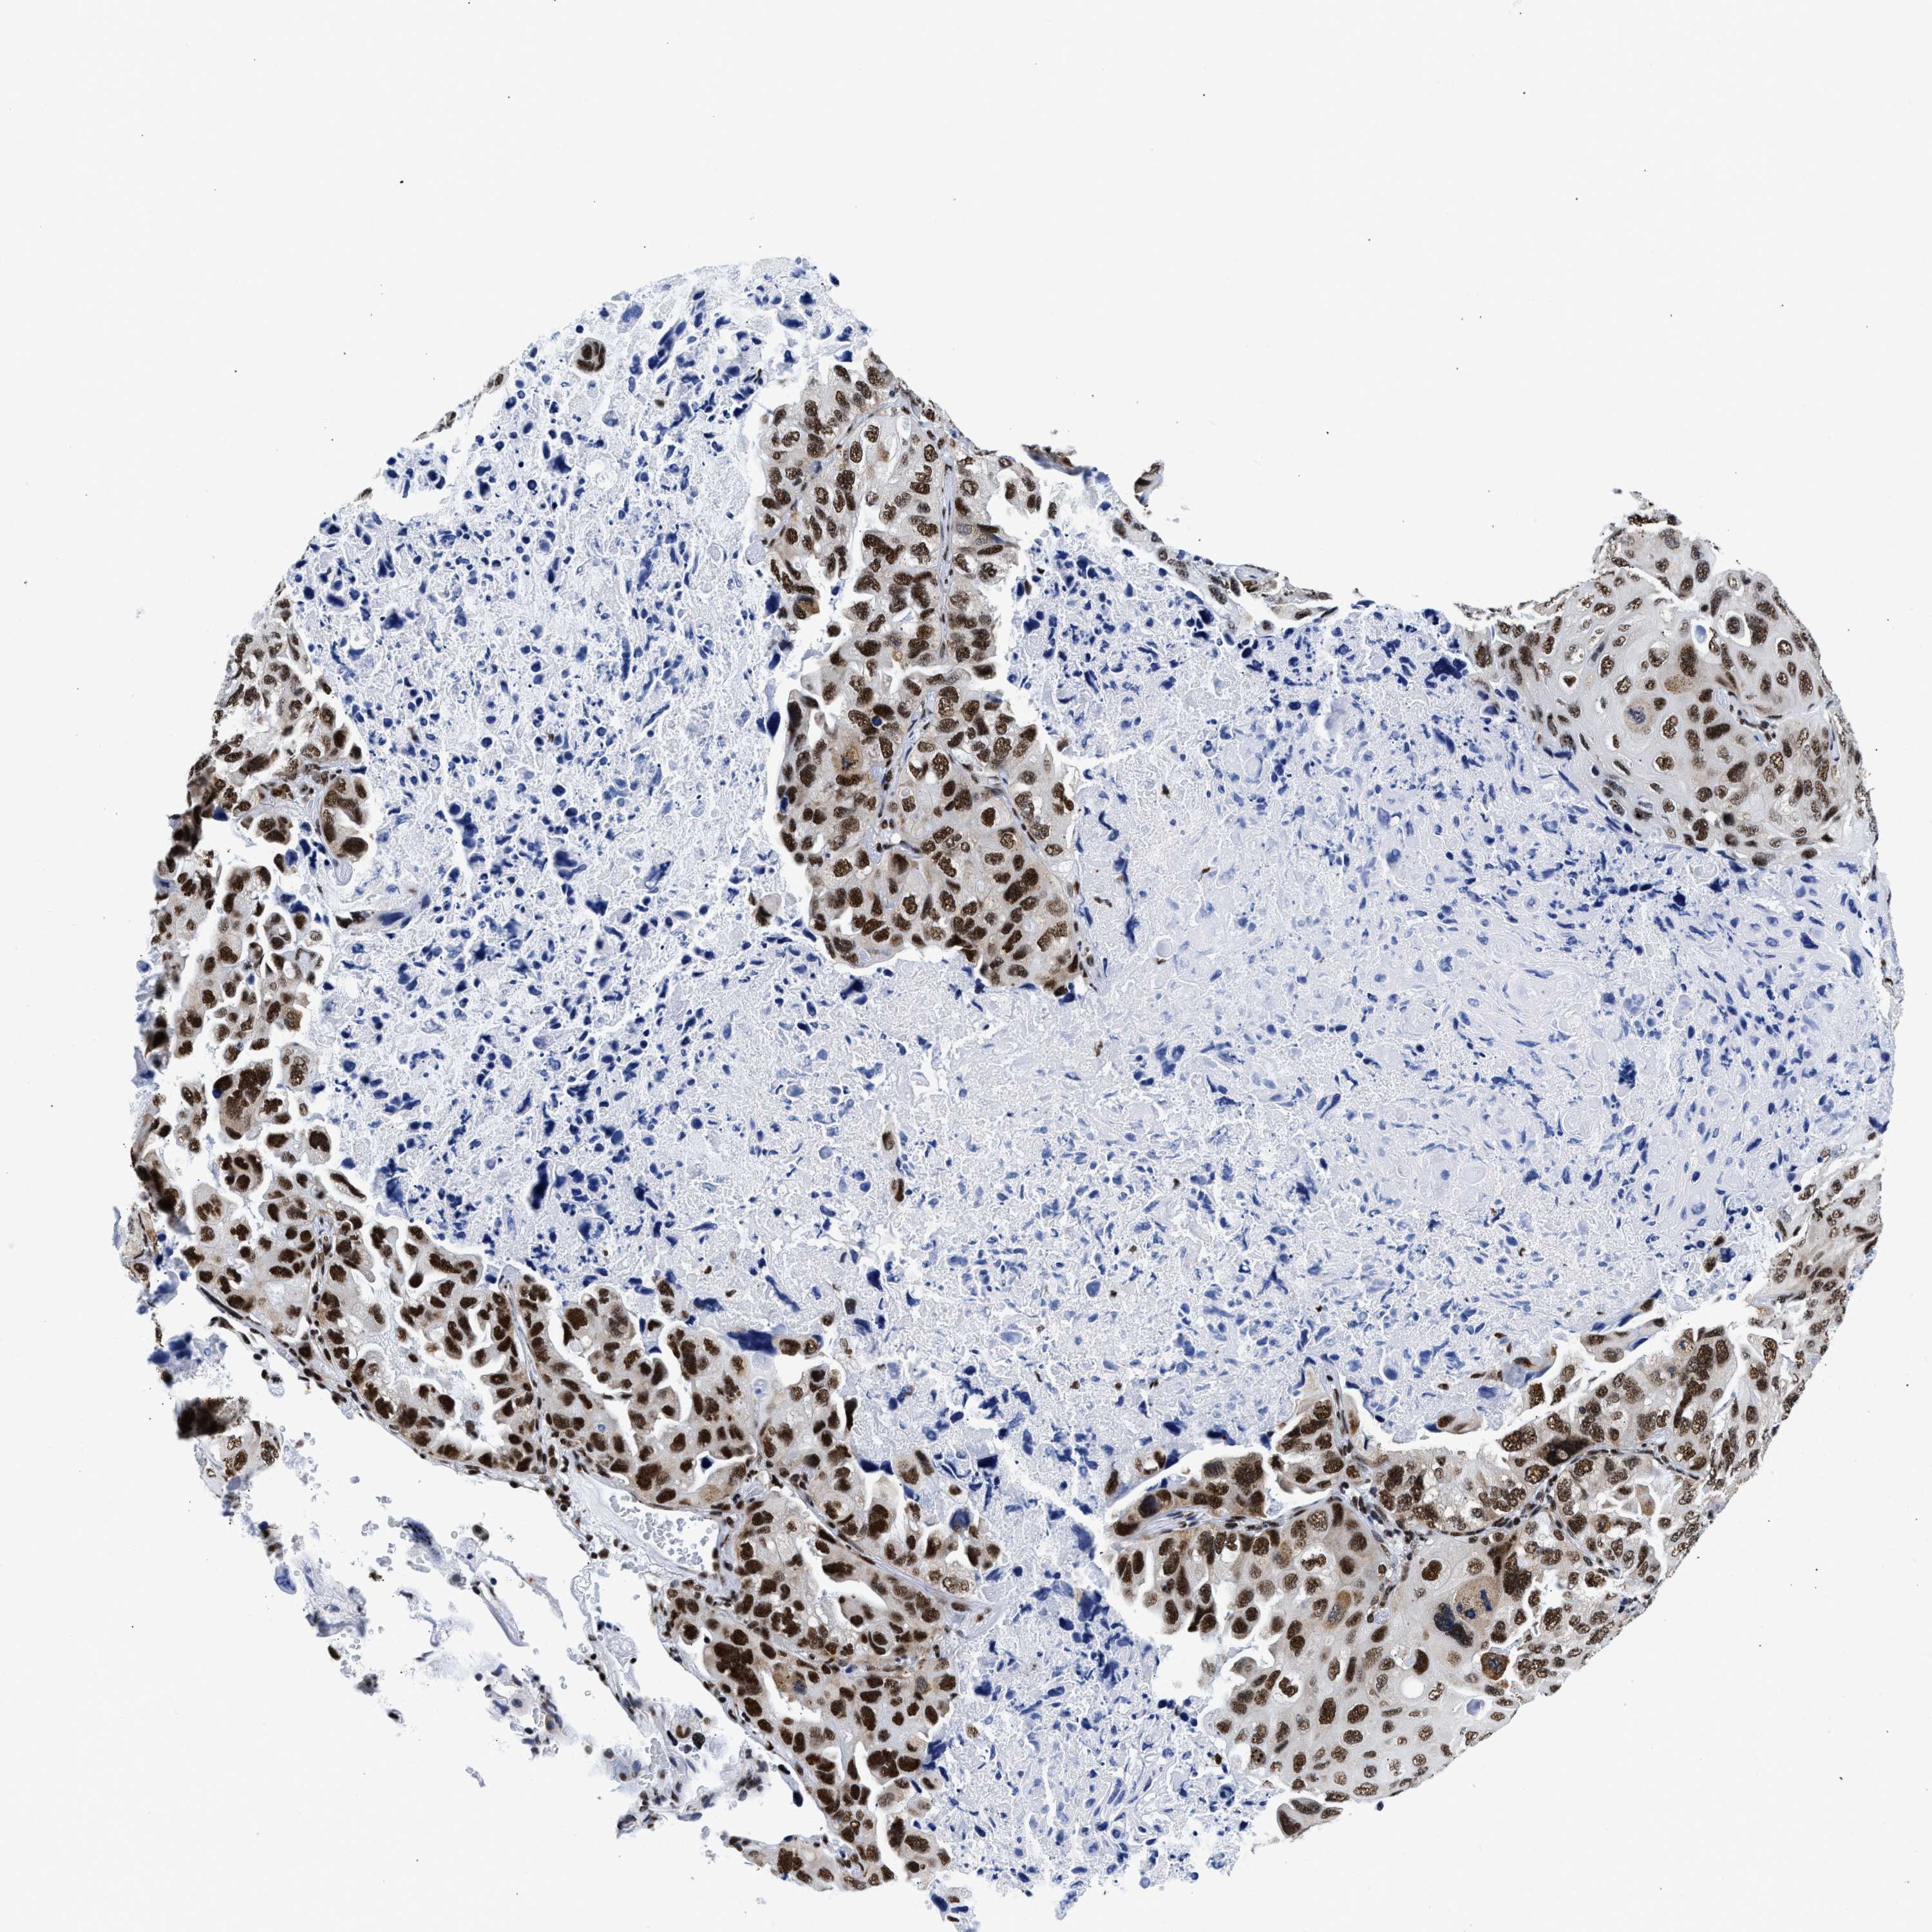

CANCER LUNG CANCER Show tissue menu